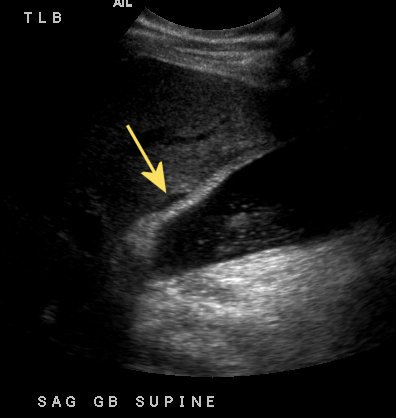

What is shown in this gallbladder ultrasound?

Pericholecystic fluid